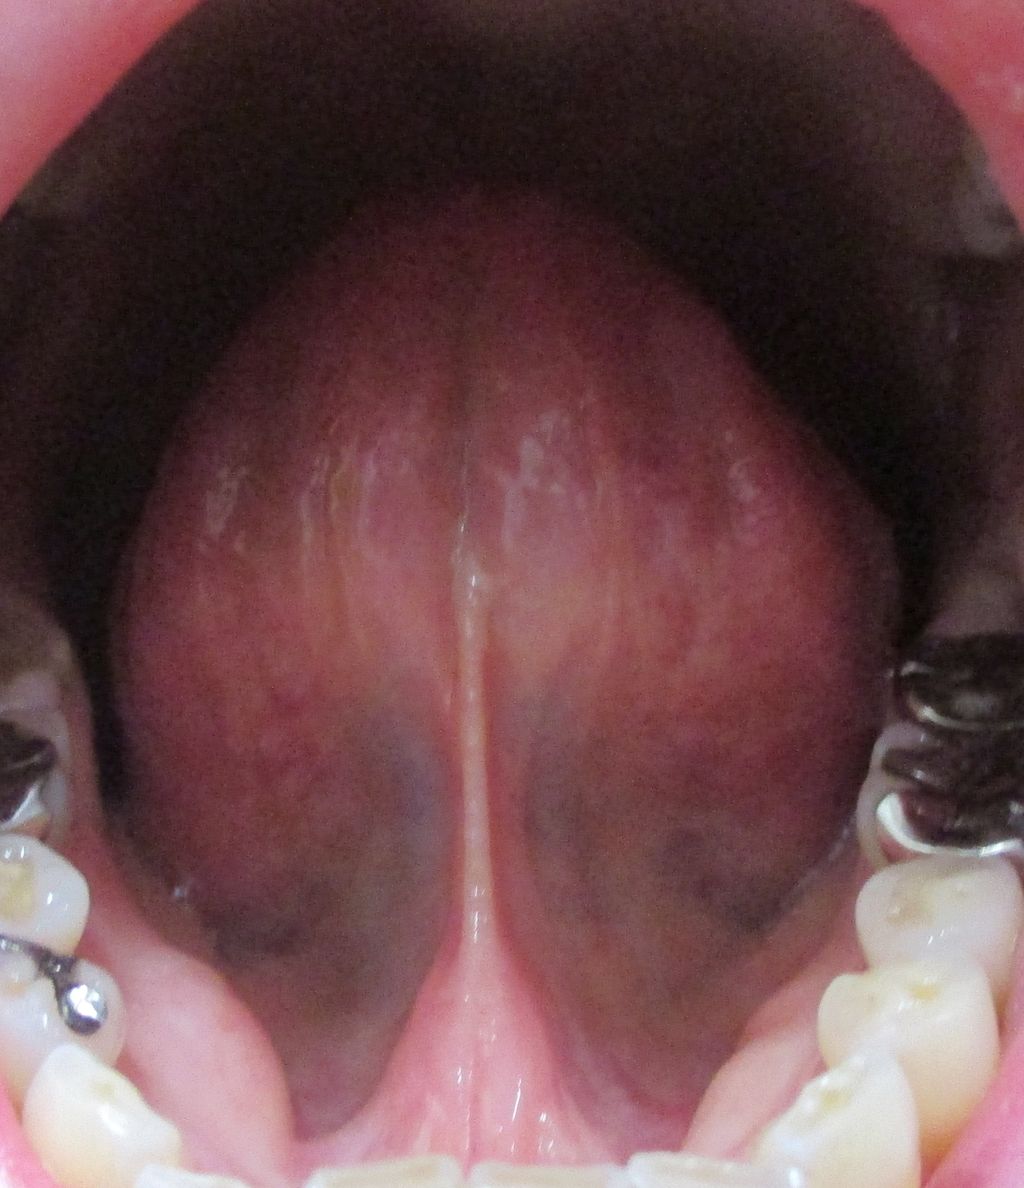

¡Ú2014ǯ1·î31Æü´ÁÊýÌôÉþÍÑÁ°¤ÎÀå¤Îɽ¡Û

¡Ú2015ǯ7·î3Æü´ÁÊýÌôÉþÍÑ518Æü¸å¤ÎÀå¤Îɽ¡Û

Àå¤Î΢

¡Ú2014ǯ1·î31Æü´ÁÊýÌôÉþÍÑÁ°¤ÎÀå¤Î΢¡Û

¡Ú2015ǯ7·î3Æü´ÁÊýÌôÉþÍÑ518Æü¸å¤ÎÀå¤Î΢¡Û